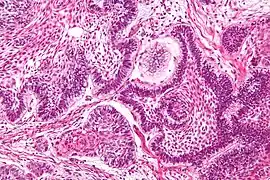

A perivascular pseudorosette consists of a spoke-wheel arrangement of cells with tapered cellular processes radiates around a wall of a centrally placed vessel. The modifier “pseudo” differentiates this pattern from the Homer Wright and Flexner-Wintersteiner rosettes, perhaps because the central structure is not actually formed by the tumor itself, but instead represents a native, non-neoplastic element. Also, some early investigators argued about the definition of a central lumen, choosing “pseudo” to indicate that the hub was not a true lumen but contained structures. Nevertheless, this pattern remains extremely diagnostically useful and the modifier unnecessarily leads to confusion. Perivascular pseudorosettes are encountered in most ependymomas regardless of grade or variant. As such, they are significantly more sensitive for the diagnosis of ependymomas than true ependymal rosettes. Unfortunately, perivascular pseudorosettes are also less specific in that they are also encountered in medulloblastomas, PNETs, central neurocytomas, and less often in glioblastomas, and a rare pediatric tumor, monomorphous pilomyxoid astrocytomas.[2]

Micrograph of perivascular pseudorosettes

Structure of a perivascular pseudorosette